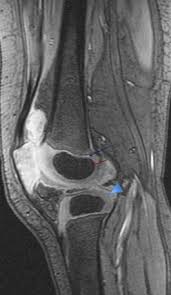

T2w axial fat sat 1. Stanford bone tumor ddx | iss/ssr msk lectures | ocad msk cases stanford msk mri atlas has served over 1,000,000 pages to users in over 100 countries. Abnormal anatomy with normal signal, i.e. Sagittal view is the basis for knee mri including acl evaluation. Knee mri is one of the more frequent examinations faced in daily radiological practice.

Mri knee anatomy scroll using the mouse wheel or the arrows. To improve delineation of acl, the knee is slightly flexed (see chap. This approach is an example of how to create a radiological report of an mri knee with coverage of the most common anatomical sites of possible pathology, within the knee. Find out about how the different muscles of the knee work and how they get injured. Magnetic resonance imaging is particularly well suited for the medical evaluation of the musculoskeletal (msk) system including the knee, shoulder, ankle, wrist and elbow. This mri knee sagittal cross sectional anatomy tool is absolutely free to use. Accessory muscles are isointense to skeletal muscle on all pulse sequences and typically attach by muscular or tendinous insertions. Anatomy of the knee can be complicated and hard to understand.

Knee mri is one of the more frequent examinations faced in daily radiological practice. Naturally, in order to assess pathologic knee imaging, it is necessary to know the appearance of a normal knee mri. Anatomical structures of the lower limb (hip, thigh, knee, leg, ankle and foot) and specific regions (compartment of the lower. A tendon connects the muscle to the bone. Stanford bone tumor ddx | iss/ssr msk lectures | ocad msk cases stanford msk mri atlas has served over 1,000,000 pages to users in over 100 countries. Atlas of knee mri anatomy. Use the mouse scroll wheel to move the images up and down alternatively use the tiny arrows (>>) on both side of the image to move the images. Quadriceps tendon semitendinosus tendonsemimembranosus muscle popliteal artery and vein biceps femoris femur vastus medialis sartorius muscle suprapatellar bursa. 12 photos of the knee muscle anatomy mri. Both the pronounced accuracy of the mri and the high prevalence of knee disorders, makes the knee mri the most frequently ordered imaging procedure of the musculoskeletal system. The knee joint is most significantly affected by two major muscle groups: If the slice thickness is 3 mm or so, it is not possible to visualize acl and pcl in their entire lengths in one plane. Plantaris can have variable size, but in most cases is difficult to demonstrate on routine mri studies.

Sagittal view is the basis for knee mri including acl evaluation. Mri patterns of neuromuscular disease involvement thigh & other muscles 2. Medical images from an mri allow medical professionals to distinguish body tissues, including the meniscus (shock absorbers in … atlas of knee mri anatomy read more » Magnetic resonance imaging (mri scan): Patellofemoral,medial femorotibial, and lateral femorotibial. Atlas of knee mri anatomy. By now you probably know that the anatomy is deceptively complex, combinations of injuries can be challenging, and of course the referring clinician's. Use the mouse scroll wheel to move the images up and down alternatively use the tiny arrows (>>) on both side of the image to move the images. Thigh muscles also protect neurovascular structures as they go through the proximal hip joint to the knee and lower leg (3). Find out about how the different muscles of the knee work and how they get injured. Three conventional mri planes that are utilized to evaluate the knee include sagittal (oblique), coronal, and transaxial planes. The knee joint is most significantly affected by two major muscle groups: Please email baodo at stanford.edu

Three conventional mri planes that are utilized to evaluate the knee include sagittal (oblique), coronal, and transaxial planes.

Intensity corresponds to a pathologic lesion. Richolt j.a., jakab m., kikinis r. In this presentation mri anatomy biceps femoris muscle. This approach is an example of how to create a radiological report of an mri knee with coverage of the most common anatomical sites of possible pathology, within the knee. By now you probably know that the anatomy is deceptively complex, combinations of injuries can be challenging, and of course the referring clinician's. T2w axial fat sat 1. This mri knee sagittal cross sectional anatomy tool is absolutely free to use. Sagittal view is the basis for knee mri including acl evaluation. Anatomy arthrogram anatomy basic shoulder mri. Anatomy arthrogram anatomy basic shoulder mri. Anatomy of the knee can be complicated and hard to understand. Anatomical structures of the lower limb (hip, thigh, knee, leg, ankle and foot) and specific regions (compartment of the lower. Abnormal anatomy with normal signal, i.e.